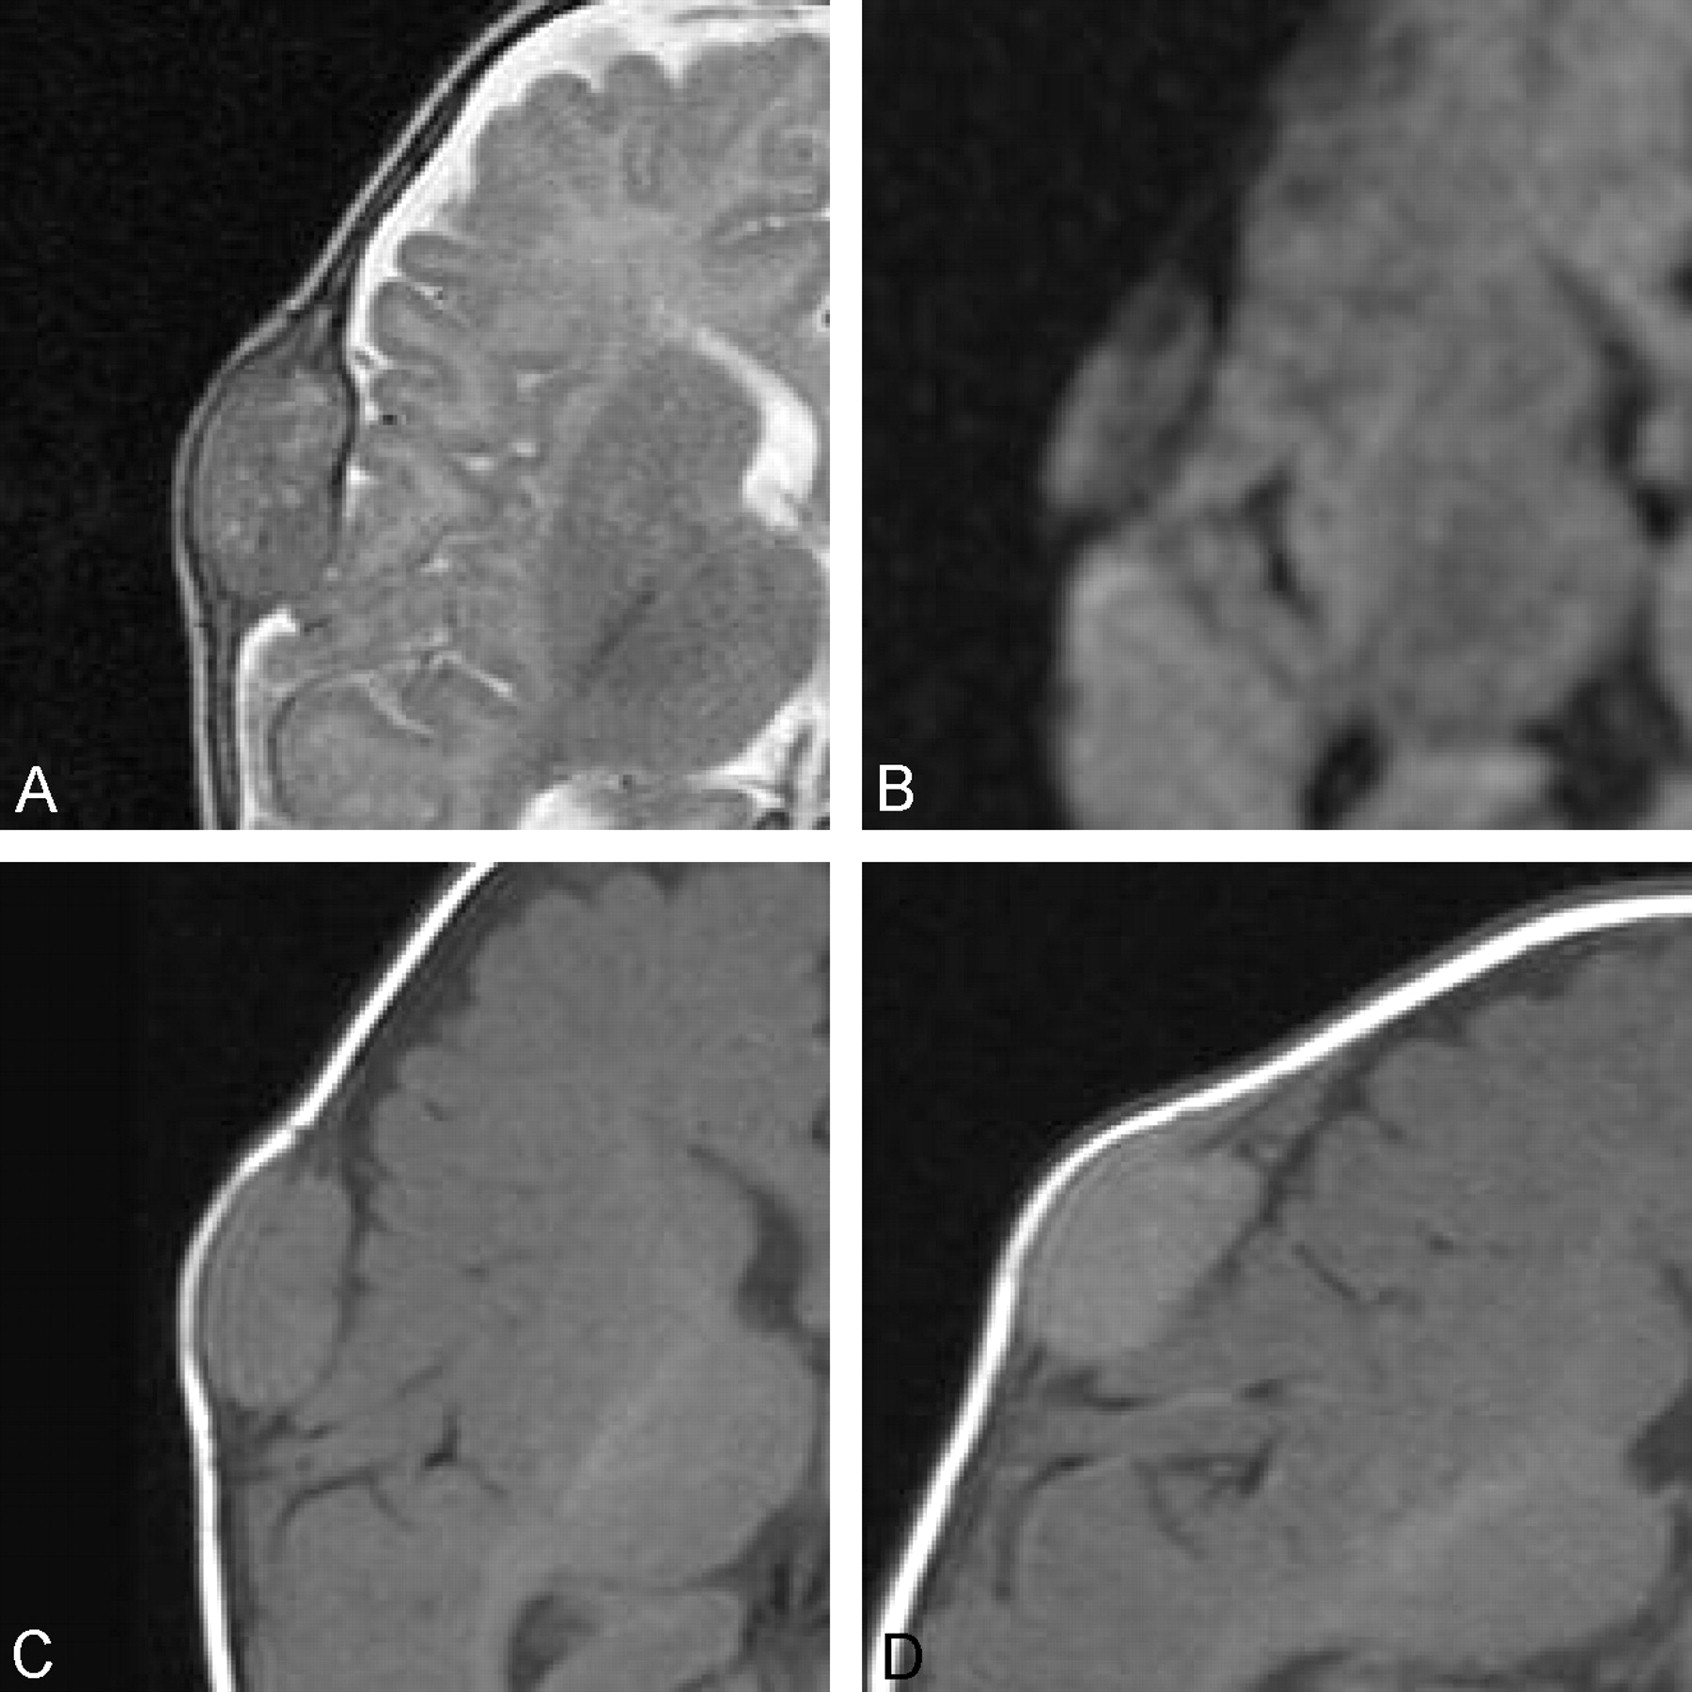

A subsequent MR image showed that the lesion destroyed both the inner and outer tables of the skull, was well defined, and demonstrated homogeneous contrast enhancement. The lesion was heterogeneous in signal intensity on T2-weighted images (Fig 3A). It showed no diffusion restriction on diffusion-weighted images, and it was isointense to gray matter on T1-weighted images (Fig 3B and C). There was also associated dural thickening and enhancement (Fig 3D). The remainder of the examination was unremarkable.

Axial T2-weighted (4780/100 [TR/TE]) (A), diffusion-weighted (b value = 1000, 5100/137 [TR/TE]) (B), and pre- (C), and postcontrast (D) T1-weighted (500/12 [TR/TE]) MR images of the brain, demonstrating cranial fasciitis of the skull as a solitary, homogeneously enhancing, extraaxial soft tissue mass centered in the calvarium. The lesion demonstrates heterogeneous T2 signal intensity, no restriction of diffusion on diffusion-weighted image, and signal intensity that is isointense to gray matter on the precontrast T1-weighted image. The postcontrast image shows enhancement of the underlying dura. There is no involvement of the underlying brain.